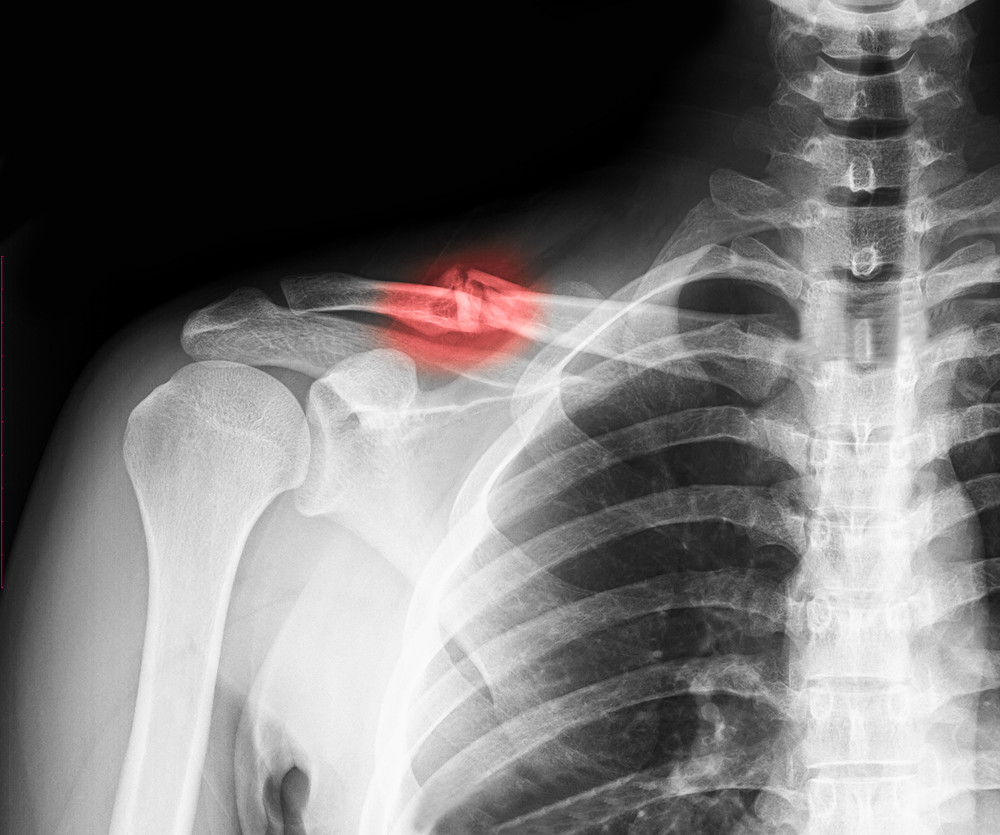

A humerus fracture is a break in the humerus, the long bone of the upper arm that runs from the shoulder to the elbow. This bone plays a key role in arm movement and shoulder and elbow function.

Humerus fractures are commonly classified based on where the break occurs:

• Proximal humerus fracture – near the shoulder joint; often seen in older adults after a fall

• Humeral shaft fracture – occurs in the middle of the bone; commonly caused by direct trauma or accidents

• Distal humerus fracture – near the elbow joint; more common with high-impact injuries

BGO Humerus Fracture